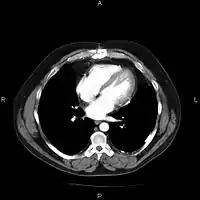

An image as stored on a picture archiving and communication system (PACS)

A picture archiving and communication system (PACS) is a medical imaging technology which provides economical storage and convenient access to images from multiple modalities (source machine types).[1] Electronic images and reports are transmitted digitally via PACS; this eliminates the need to manually file, retrieve, or transport film jackets, the folders used to store and protect X-ray film. The universal format for PACS image storage and transfer is DICOM (Digital Imaging and Communications in Medicine). Non-image data, such as scanned documents, may be incorporated using consumer industry standard formats like PDF (Portable Document Format), once encapsulated in DICOM. A PACS consists of four major components: The imaging modalities such as X-ray plain film (PF), computed tomography (CT) and magnetic resonance imaging (MRI), a secured network for the transmission of patient information, workstations for interpreting and reviewing images, and archives for the storage and retrieval of images and reports. Combined with available and emerging web technology, PACS has the ability to deliver timely and efficient access to images, interpretations, and related data. PACS reduces the physical and time barriers associated with traditional film-based image retrieval, distribution, and display.